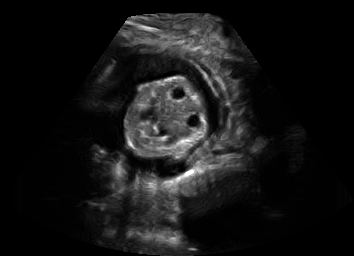

Real in-vivo images. 22 ultrasound sequences were collected using a GE Voluson E8 machine during standard fetal screening exams of 8 patients. Each sequence is several seconds long. We extracted all 4427 frames and resize them to , see Fig. 2 for some examples. The resulting image set was randomly split into training-validation-test sets by a 80-10-10% ratio.